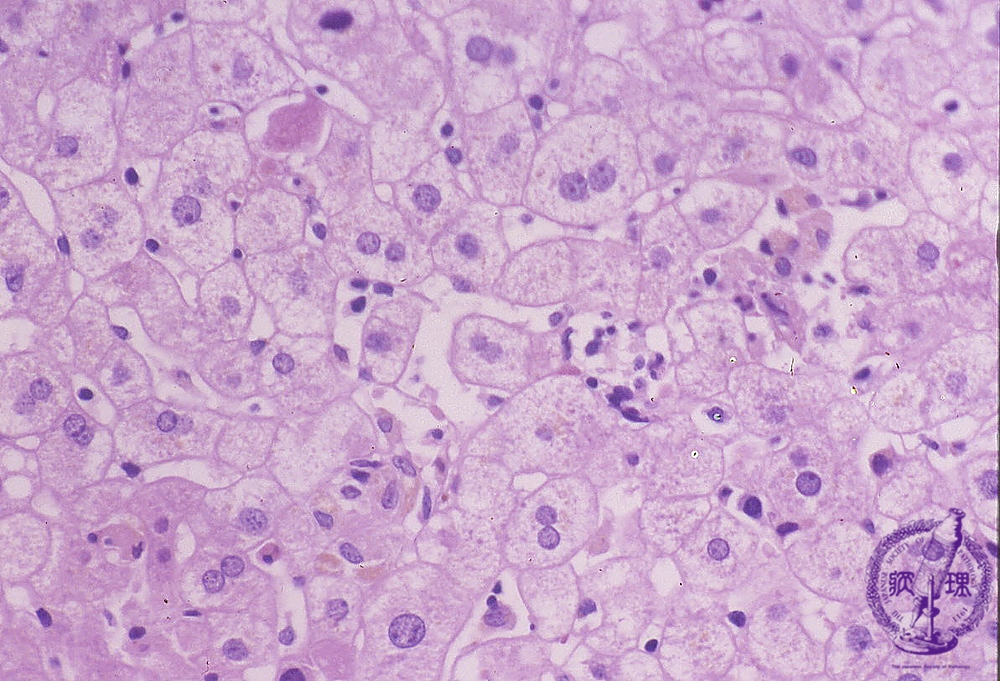

- ★(1)Acute viral hepatitis

Microscopic finding (HE stain, high power view): There is multifocal patchy lobular necrosis scattered throuought and eosinophilic bodies are also seen. Swollen Kupffer cells, pigment laden histiocytes and infiltrating lymphocytes are observed within sinusoids.